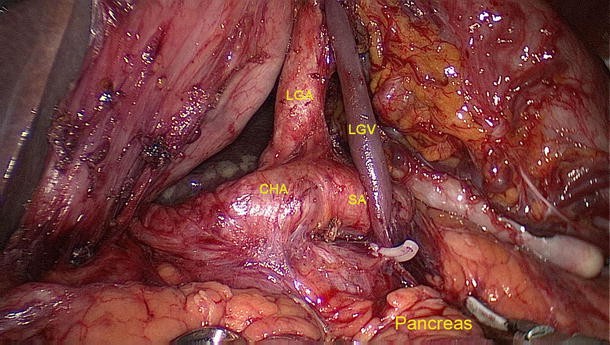

Of the 2,111 gastric cancer patients who underwent radical resection, 6 had the rare anatomic variant of the LGV patients (Figs. 4, 5, 6, 7); the incidence of this finding was about 0.28 %. Its specific drainage pattern differed from that of the normal LGV. In patients with the variant, small vessels from the anterior and posterior walls of the lesser curvature of the stomach drained into the LGV. It lay close to the LGA in the large part of the lesser curvature, descended along the gastropancreatic fold, ran across the dorsal side of the splenic artery and drained into the splenic vein. These vascular anatomies in six patients were documented by the high definition images during laparoscopic-assisted radical gastrectomy.

Fig. 7

figure 7

LGV running across the dorsal side of the splenic artery. LGV left gastric vein, LGA left gastric artery, CHA common hepatic artery, SA splenic artery